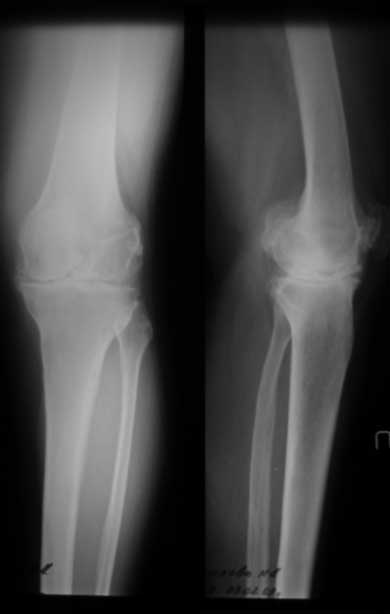

По данным R-грамм, хотя качество их не очень..., мне кажется имеется 2 основных ошибки: 1. высокий уровень остеотомии большеберцовой кости, при разгибетельных контрактурах его необходимо делать ниже.

2. Большой размер бедренного компонента. За счет этого переднезадний размер увеличен и ограничивает сгибание.

снимки